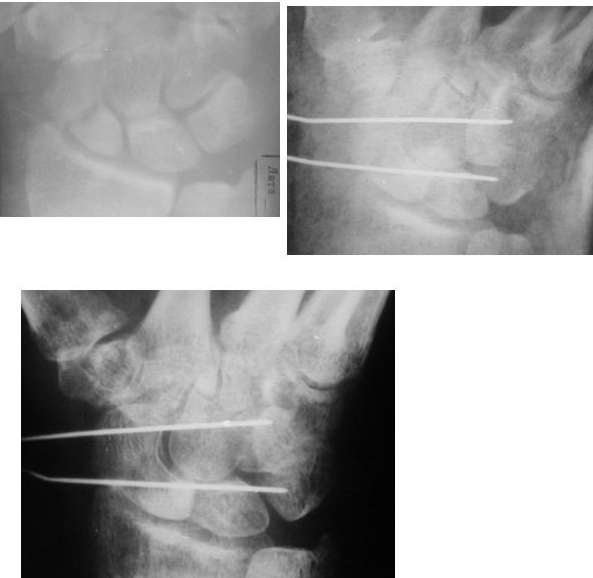

I am not sure if the differential of a nonunion vs. pseudoarthrosis means much in this context. The distal pole of the screw has a lucency, so the

nonunion is most likely unstable and moving. It needs revision. The radial styloid does not have evidence of DJD, so I do not think it needs to be resected. The surgery will probably require an open revision, removal of necrotic bone and soft tissue interposition, and would benefit from some

distal radial autograft. The patient needs to refrain from smoking and I would use a case to be sure they do not move for a while. A stiff wrist is not a bad outcome; a bad outcome is a painful wrist.

Такое ощущение, что имеющееся состояние ещё не является необратимым (отсутствие склероза отломков на уровне перелома) и обусловлено исключительно нестабильностью (сам винт оказался слабоват или чрезмерные нагрузки привели к срыву фиксации - пациент, заметьте, мотоциклист!)

Почему-то хочется верить, что можно добиться сращения, если вернуть кости стабильность путём компрессионного остеосинтеза более мощным винтом без открытого вмешательства на компрометированной зоне и защитить фиксацию строгим соблюдением режима. Я сильно ошибаюсь?

Ув. Данил! По моему мнению все-таки ложный сустав -склероз отломков (приложение), 5 мес, диастаз. Для подтверждения можно выполнить КТ кистевого сустава (формирование замыкательной пластинки, склероз концов отломков и т.д.,), а так же по КТ можно выявить сохраняется ли подвывих каких-либо костей запястья или нет. При наличии ложного сустава целесообразно будет удалить винт,обработать концы отломков, разрушив замыкательные пластинки и выполнить остеосинтез ладьевидной кости винтом с костной аутопластикой зоны псевдоартроза (либо гидроксиаппатитом...) Гипс 1,5 мес мин. Снимков найти сейчас не получилось. позже дошлю.